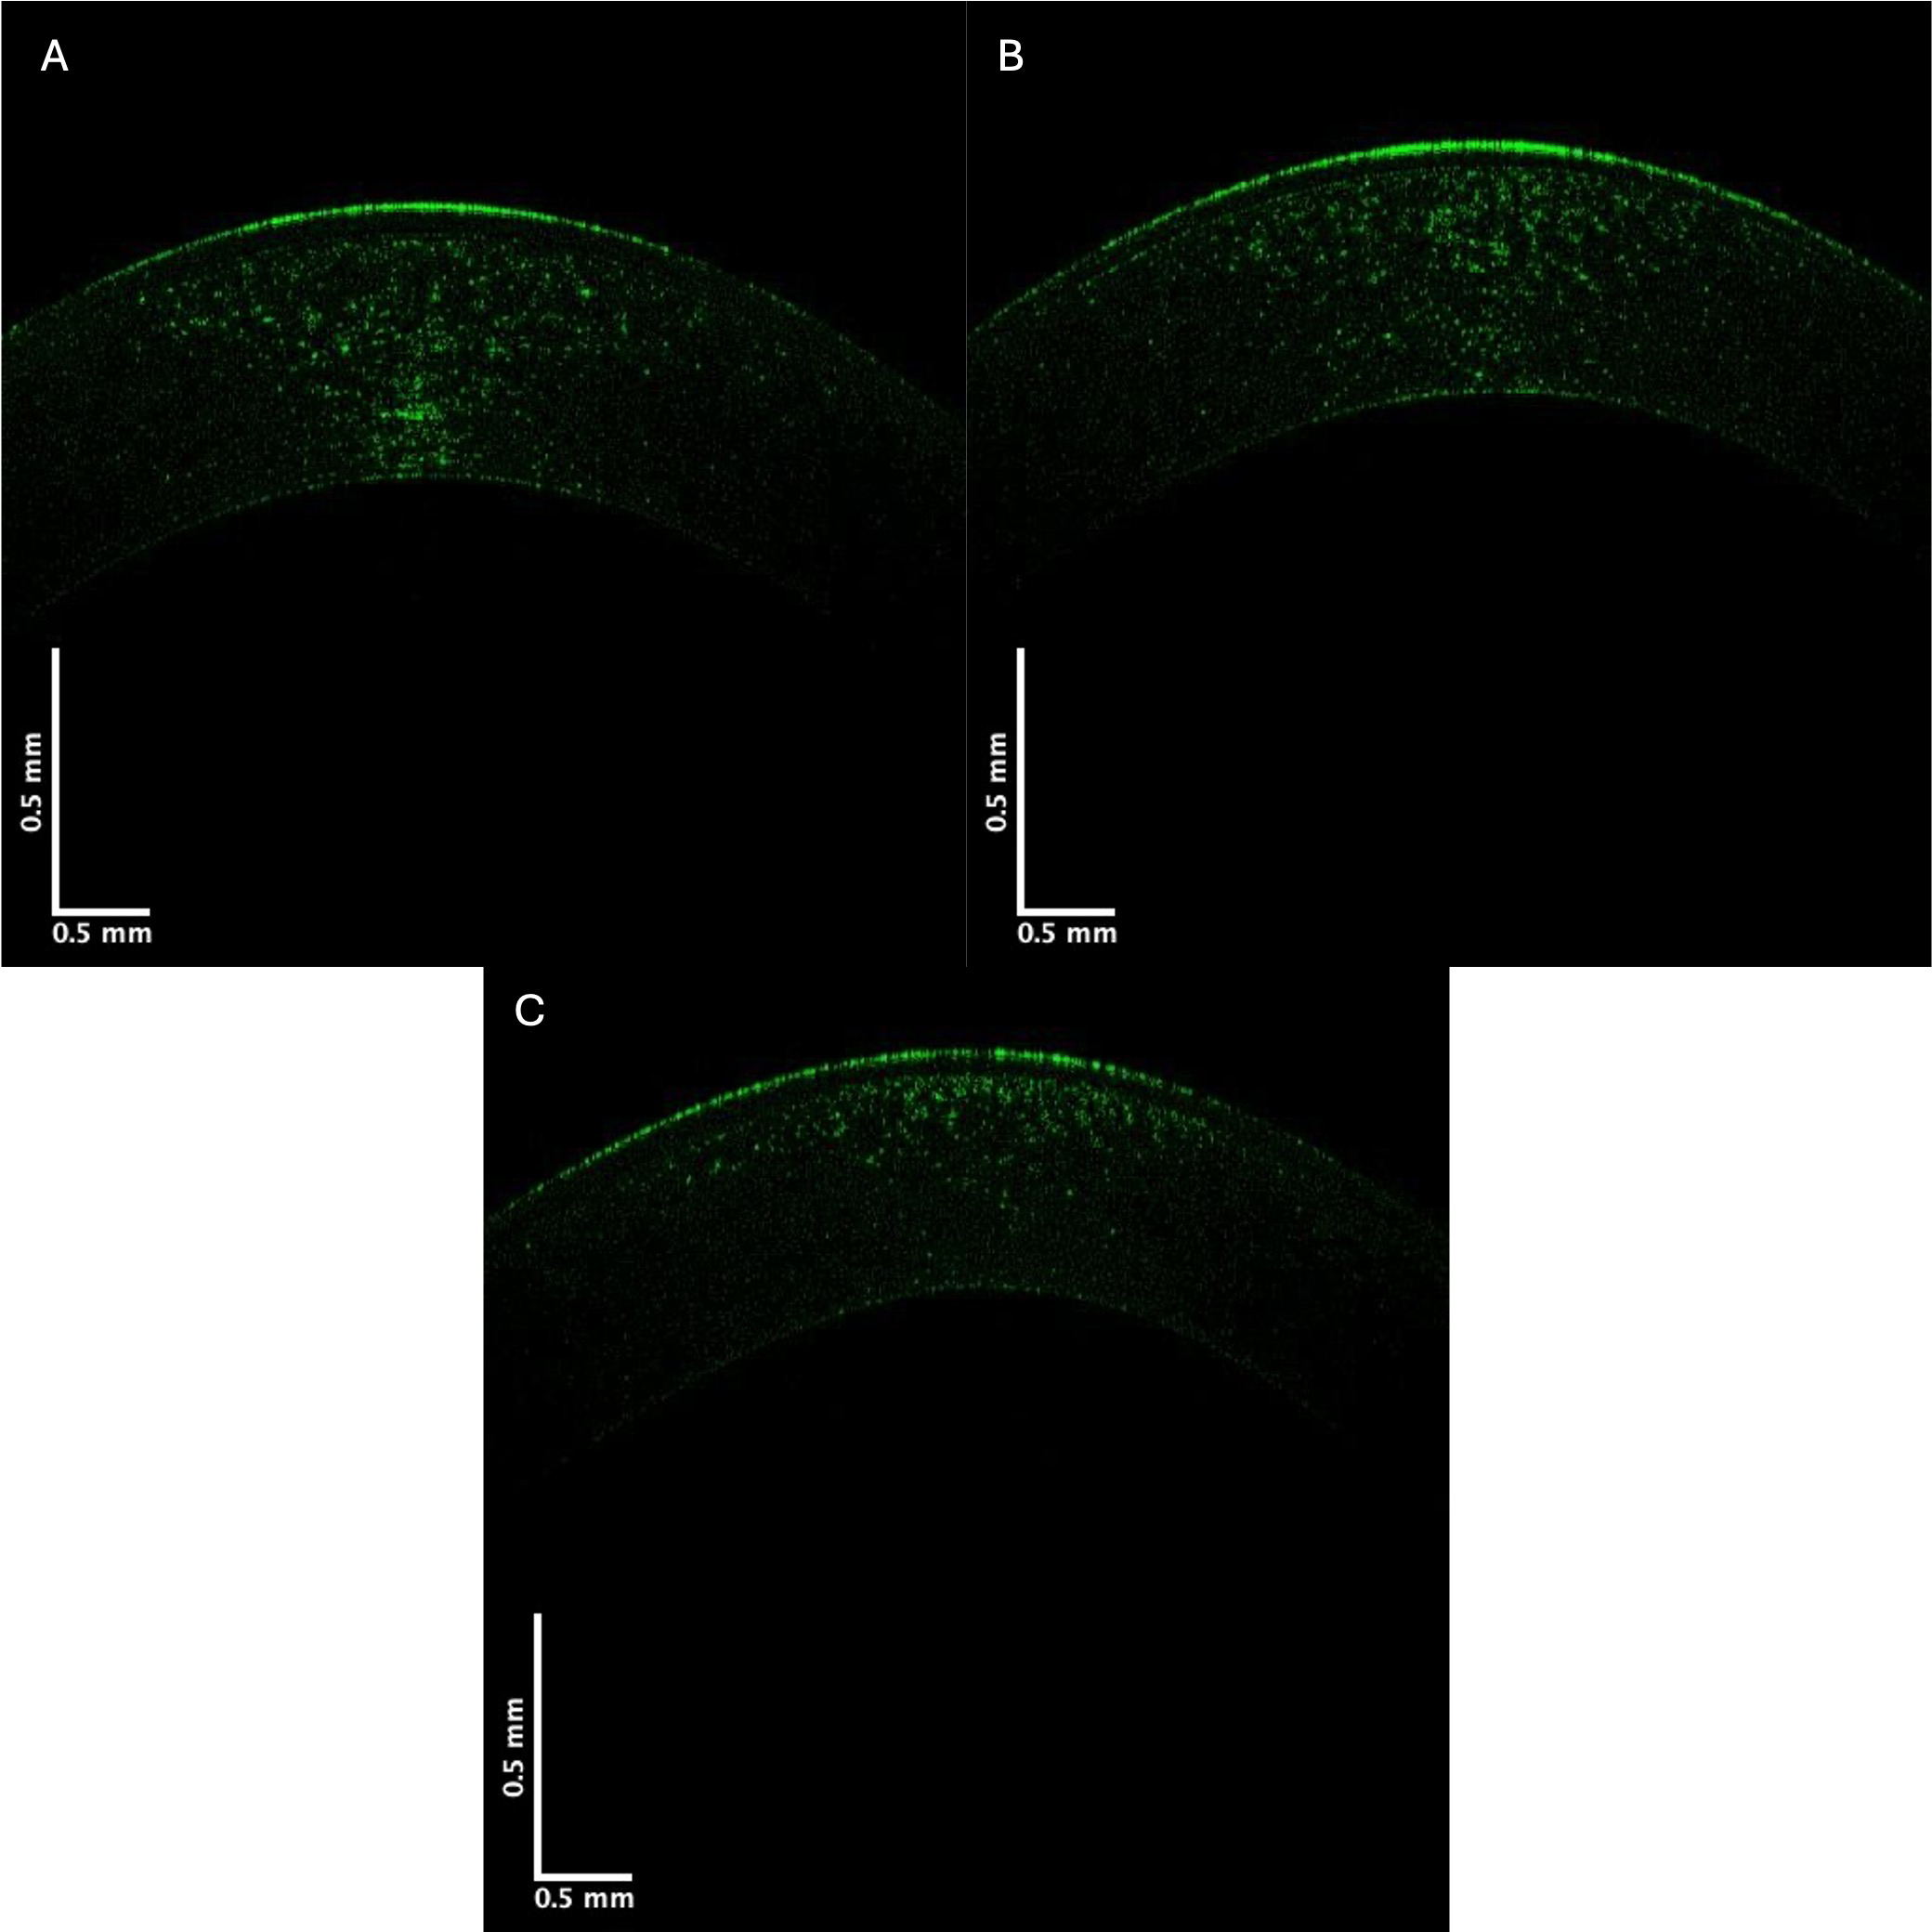

The control and KC cornea images were compared when the grayscale images of the control and KC corneas were separated into individual low (green), medium (blue), and high (red) pixel intensities. Fig. 3 shows the OCT images of the central cornea green channel in typical control (A), Stage II (B), and Stage IV (C) KC corneas. Note the decreased green channel pixel intensity in the posterior central cornea compared to the control and Stages III and IV corneas (Fig. 3).

Fig. 3. Typical green central cornea subchannel images of control (A), Stage II (B), and Stage IV (C) KC corneas. Note the apparent decreased pixel intensity in the posterior region of the corneas in Stages II and IV KC, which suggests a loss of cells (keratocytes) in the posterior cornea.

Pixel intensity versus depth plots for the green channel are shown in Fig. 4. Previous studies on skin demonstrated that the green channel represents the low-intensity cellular contribution to the reflected light [12]. The images in Fig. 4 show that the decreased cellular contribution, presumably of the keratocytes, to the green image decreases in KC.

Fig. 4. The pixel intensity versus depth of the central cornea green channel for control (A), Stage II (B), and Stage IV (C) KC corneas—based on Fig. 3. Note the decreased pixel intensity at depths below 0.1 mm in Stages II and IV in the KC plots suggesting a decrease in the number of keratocytes in posterior corneas. Arrows indicate the points between which the slope was calculated.

The decrease in the initial slope of the pixel intensity versus depth plot for the green channel of Stages I and II KC corneas was statistically greater than that of the control. In contrast, the corneas of Stages III and IV were not statistically different in the data presented in Table 4. These data suggest that the cellular content of the anterior corneas decreases rapidly in the early stages of KC. Table 5 illustrates the pixel intensity of the green channel at a depth of 0.25 mm, which was significantly different for Stage IV but not Stage II at a p-value